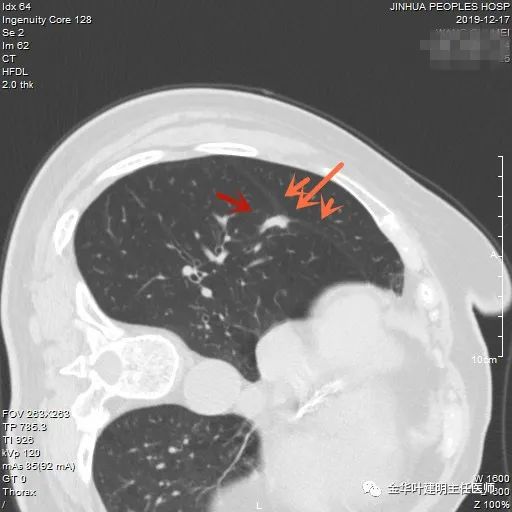

上图示浸润性腺癌典型表现。实性结节,有细毛刺征,有血管进入病灶,部分地方有浅分叶。